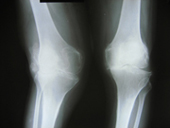

Arthritis both knees varus deformity pre op Post op Total Knee Replacement Post op Total Knee Replacement